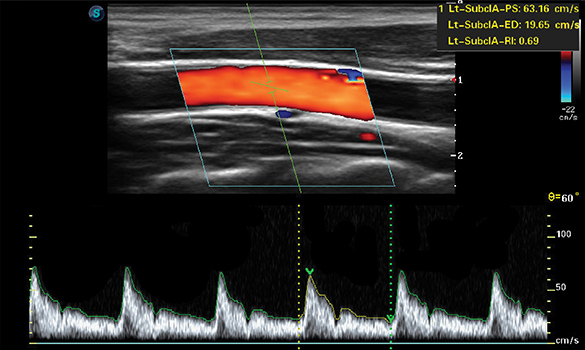

Auto IMT

Automatically calculates intima-media thickness for fast, consistent vascular assessment.

Auto Trace

Automatically traces Doppler waveforms to enable fast and accurate hemodynamic measurements.